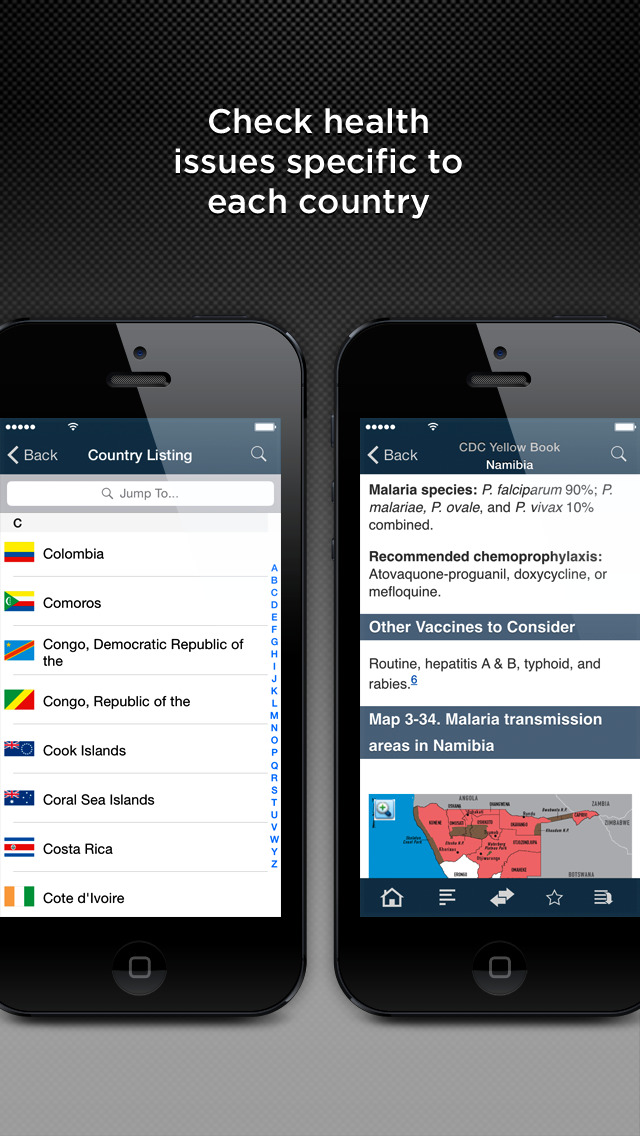

CDC YELLOW BOOK (Health Information for International Travel)

The Yellow Book presents advice on any travel health issue including vaccinations, essential trip planning and safety tips, prevention of an expanded list of travel-related infectious diseases, altitude illness, motion sickness, sunburn, medical tourism, and much more.